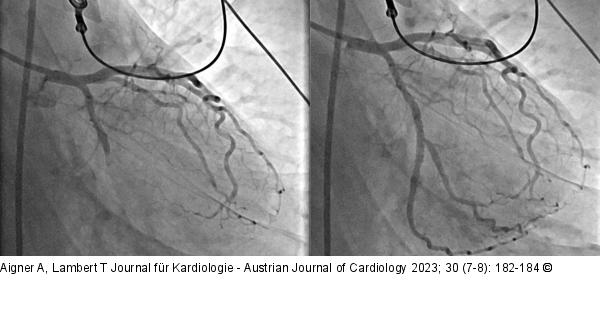

Abbildung 4: Koronarmorphologie Darstellung der Koronarmorphologie der linken Koronararterie. Im linken Bild zeigt sich der Ramus circumflexus verschlossen. Im rechten Bild kommt nach der akuten Revaskularisation distal der Verschlussstelle eine Bifurkation zur Darstellung, deren Äste sowohl antero- als auch posterolaterale Areale des linken Ventrikels versorgen. |